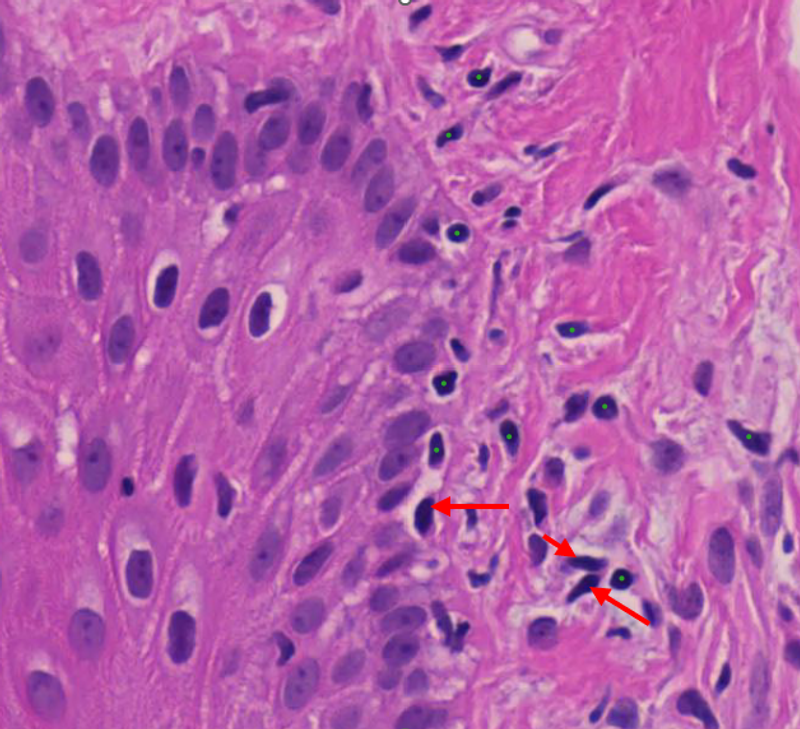

Figure 2. Labeled (green dots) versus unlabeled-but-similar (red arrows) cells in a single H&E tile. The model has no way of knowing the arrow-marked cells belong to the same class.

For a detection model (e.g. RF-DETR, YOLO), this is brutal. The model looks at a tile with ten visible lymphocytes, only three of which got labeled, and learns that the other seven are "not lymphocytes." Every time it correctly spots a lymphocyte on an unlabeled cell, it gets penalized, and the gradient pulls the model away from detecting the very thing you're trying to teach it. This is an active problem in object detection, known as the sparse annotation problem (Wu et al., 2019; Niitani et al., 2019).

For a classifier, it's sneakier but no less damaging. The model carves out a decision boundary tight around whatever subset of cells happened to get labeled, while cells outside that subset get pushed into other classes. Your validation accuracy on the labeled subset looks fine, but real-world performance is mysteriously poor. And you can't see this from inside the dataset. Every metric you check is evaluated against the same biased labels, so the model looks like it's working because it's being graded against the same flawed answer key it studied from.